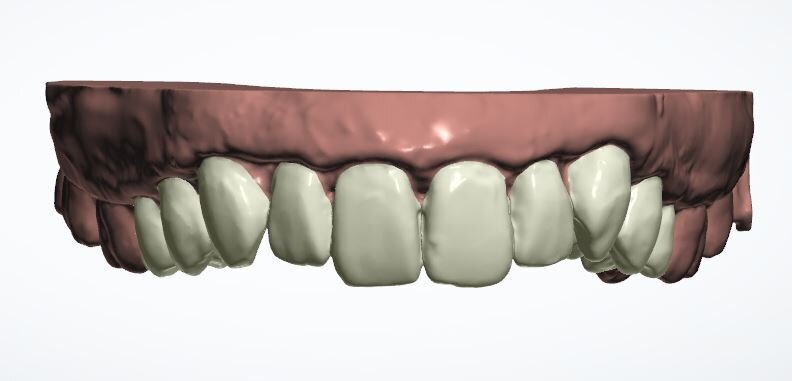

Two weeks later, the colour and contour of the patient’s gingival margins were as healthy as could be considering the crowding of the teeth. We discussed what treatment with ClearSmile Aligners would involve, such as interproximal reduction (IPR), compliance and risks, and a referral for specialist orthodontics was offered. Preferring to proceed with clear aligners, the patient signed off his full consent, and a two-stage putty impression was taken using a separation wafer. The Archwize digital planning software was used to predict tooth movement and necessary IPR throughout treatment. It suggested that 18 maxillary aligners would be needed.

At the end of the 18 planned aligners, there was still a central diastema of approximately 0.2 mm and tooth #23 had not rotated completely. The laboratory offered three (free) or six (for a fee) refinement aligners. The patient chose the latter, reasoning that as we had come this far, we should finish properly. He was charged the laboratory cost only.

Fig. 13a: Current position

Fig. 13b: Three refinement aligners

Fig. 13c: Six refinement aligners